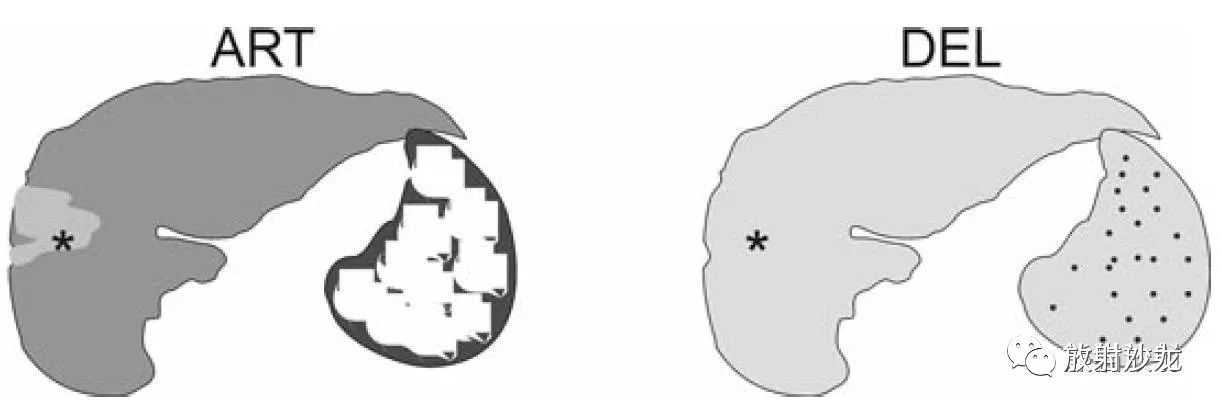

ART:动脉期有强化,可能提示HCC;

DEL:延迟期右叶病灶持续强化呈等信号,提示融合性纤维化。

肝硬化,融合性肝硬化,MRI表现:

A~D:影像表现同上方所述。